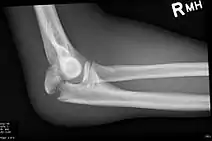

Olecranon fracture is a fracture of the bony portion of the elbow. The injury is fairly common and often occurs following a fall or direct trauma to the elbow. The olecranon is the proximal extremity of the ulna which is articulated with the humerus bone and constitutes a part of the elbow articulation. Its location makes it vulnerable to direct trauma.

To assess an olecranon fracture, a careful skin exam is performed to ensure there is no open fracture. Then a complete neurological exam of the upper limb should be documented.[5][2] Frontal and lateral X-ray views of the elbow are typically done to investigate the possibility of an olecranon fracture.[1] A true lateral x-ray is essential to determine the fracture pattern, degree of displacement, comminution, and the degree of articular involvement.